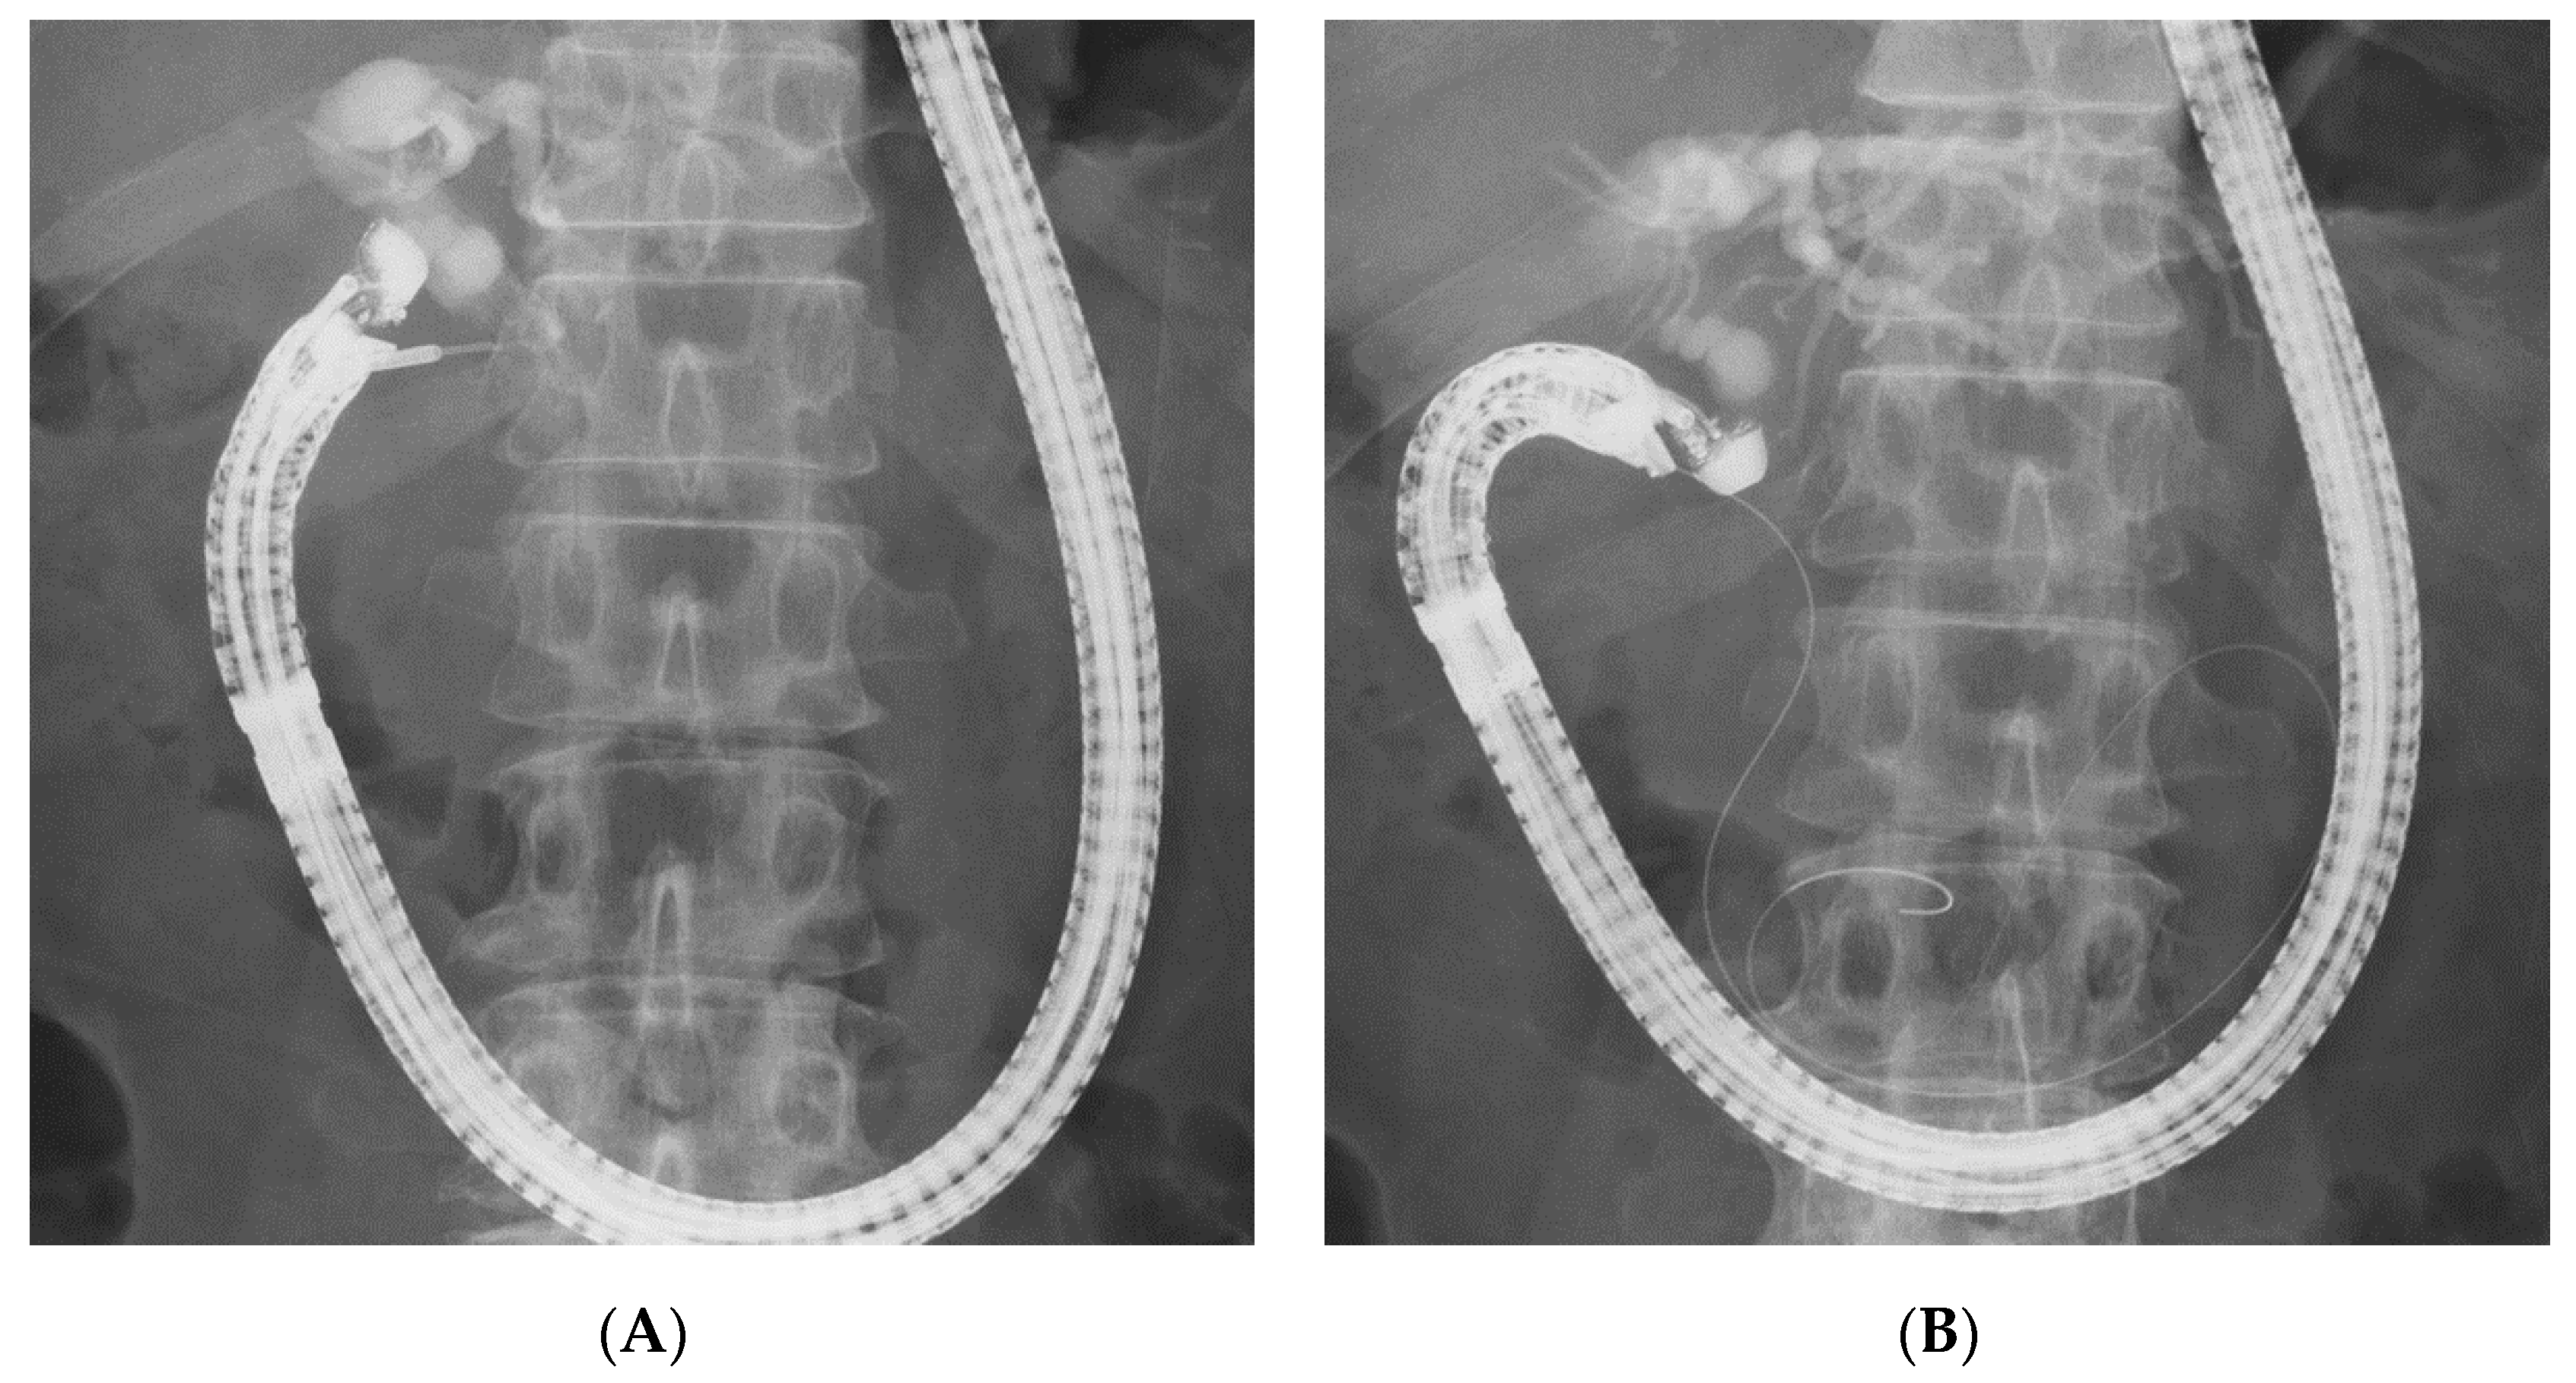

2.5. Biliary Cannulation Methods during EUS-RV

3.5. Cannulation Methods

| Cannulation method, n (%) | 0.86 | ||||

| Over-the-wire | 2 (20) | 1 (20) | 1 (100) | 0 | |

| Along-the-wire | 4 (40) | 1 (20) | 0 | 0 | |

| Hitch-and-ride | 4 (40) | 2 (40) | 0 | 1 (100) | |